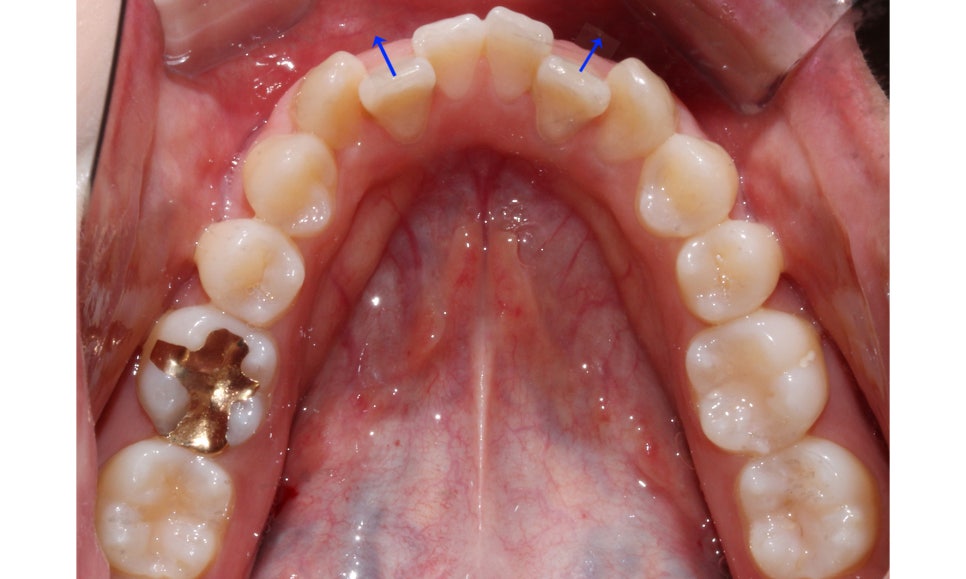

송곳니덧니 case의 상악 교합면 사진을 보시면

송곳니의 위치가 심하게 어긋나 있는 모습을 볼 수 있습니다.

부분교정의 경우 교정장치 부착의 기준이 되는

송곳니(견치)의 위치가 큰 영향을 받기 때문에

위의 Case처럼 기준치의 위치가 틀어진 경우

부분교정보다는 전체교정을 추천드립니다.